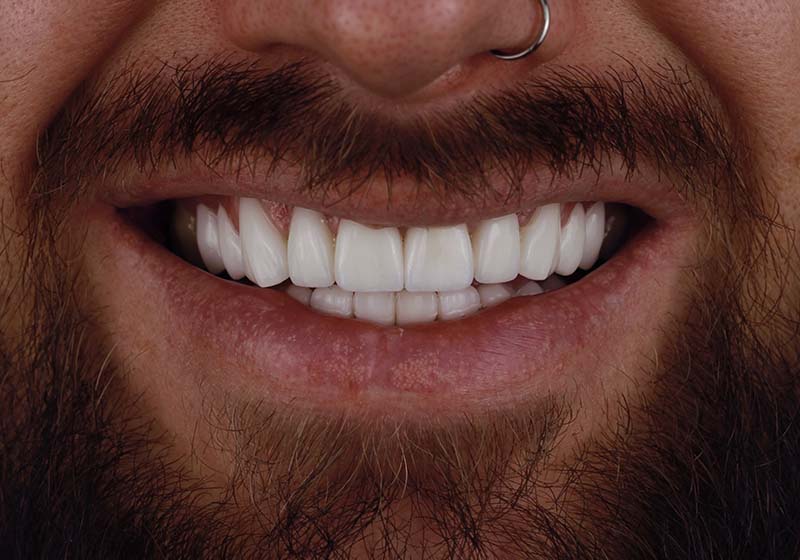

Виниры из цельной керамики E-Max для зоны улыбки

Пациент обратился с жалобами на эстетику фронтальной группы зубов: потемнение, дефекты эмали, неровность режущего края и передних стенок зубов. Был установлен комплекс цельнокерамических виниров на всю зону улыбки верхней челюсти.